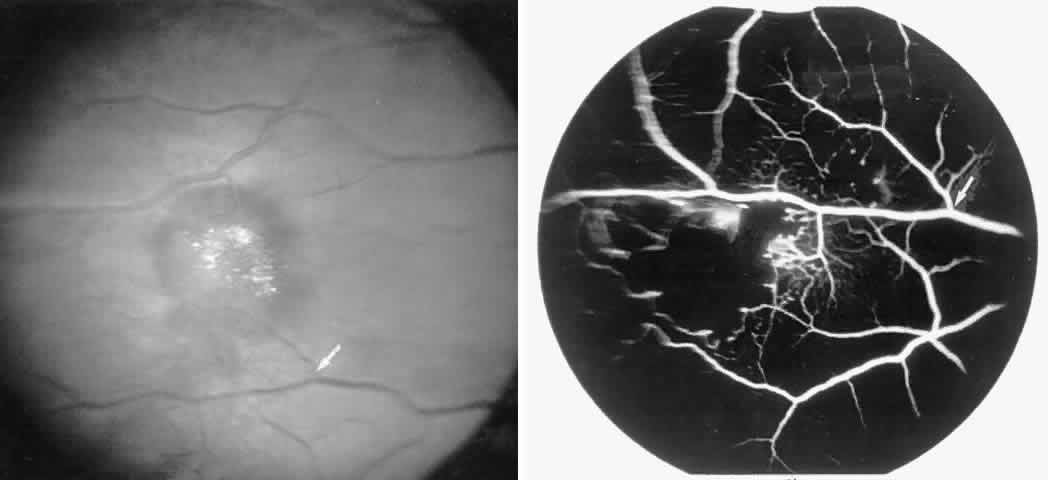

Macular Small Vessel Occlusions

Occlusions of the fine vasculature of the macular and perimacular area have been reported in 10% to 40% of patients with sickle cell disease.18,83,91–99 In the acute phase, the occluded vessel will have a dark red appearance and may appear as a dark line on fluorescein angiography (Fig. 9). Nerve fiber layer infarcts (cotton-wool spots) are seen (see Fig. 8D and E;Fig. 10).100

Fig. 9. A 27-year-old man with homozygous sickle cell anemia. A. Fluorescein angiogram of the right eye shows multiple arteriolar occlusions temporal to the fovea (arrows). B. Same area 6 months later shows more extensive occlusions. The black arrowheads (A and B) identify corresponding arteriolar bifurcation.

Fig. 10. A 33-year-old woman with SC disease and stage III sickle cell retinopathy. A. Photograph of the right eye shows a cotton-wool spot with a dark segment identifying the occluded vessel (arrow). B. Fluorescein angiogram demonstrates nonfilling of the occluded vessel (arrow). C. Eighteen months later, the occluded vessel is still visible (arrow). D. Fluorescein angiogram demonstrates that there is still nonfilling of the vessel (arrow).